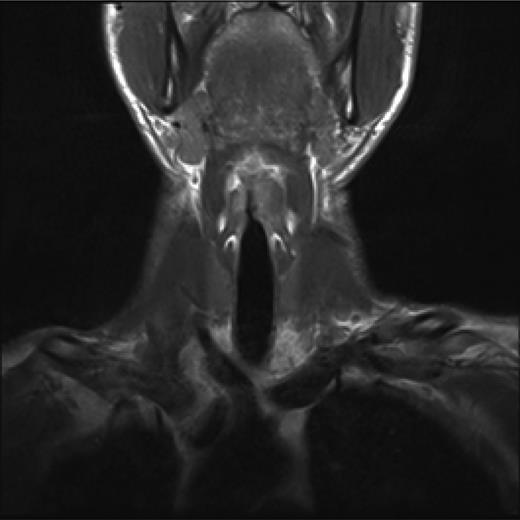

Post treatment with CO2 laser, the patient underwent a T1 weighted magnetic resonance imaging (MRI) with gadolinium of the neck. The imaging demonstrated an abnormal soft tissue density in the left supraglottic region (Figs 3 and 4). The low intensity lesion was 9 × 4 mm in size and caused distortion of the left aryepiglottic fold and minor airway narrowing. The findings on MRI suggested the persistence of disease.

Coronal view, T1 weighted MRI neck showing abnormal low intensity foci in the left false vocal cord.